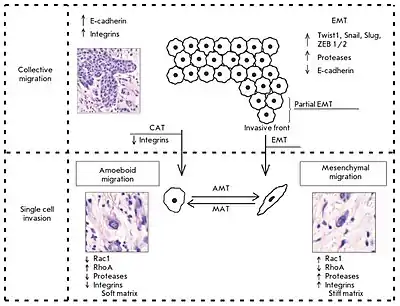

There exist two main patterns of cancer cell invasion by cell migration: collective cell migration and individual cell migration, by which tumor cells overcome barriers of the extracellular matrix and spread into surrounding tissues. Each pattern of cell migration exhibits distinct morphological features and is governed by specific biochemical and molecular genetic mechanisms.

Two types of migrating tumor cells, mesenchymal (fibroblast-like) and amoeboid, can be observed in various patterns of cancer cell invasion. This article describes the key differences between the variants of cancer cell migration, the role of epithelial-mesenchymal and related transitions, as well as the significance of different tumor factors and stromal molecules in tumor invasion. Morphological manifestations of the invasion patterns are characterized by a variety of tissue (tumor) structures.[2]

Two distinct patterns of invasive growth are distinguished based on specific morphological and molecular genetic parameters: single-cell migration and collective cell migration. The migration type is predominantly influenced by characteristics of the tissue microenvironment, and is dependent on molecular changes within the tumor cells.

Single cell invasion is distinguished by individual tumor cells invading the surrounding tissues independently of each other. In this type of tumor invasion, single cell migration can occur via two different movement types: mesenchymal and amoeboid. These movement types are highly plastic and can shift from one type of migration to the other (from mesenchymal to amoeboid and vice versa). These transitions usually occur upon changes in the activity of certain cell molecules when tumor cells have to adapt to the peculiarities of the microenvironment.[2]

Amoeboid-mesenchymal and mesenchymal-amoeboid transitions

There exists a degree of plasticity and the possibility of a "shift" from one migration type to the other (from the mesenchymal type to the amoeboid one and vice versa) upon individual cell invasion. These events are due to the appearance of changes in the activity of certain cell molecules and the need to adapt to tissue microenvironment conditions.[2]

These changes are described as amoeboid-mesenchymal and mesenchymal-amoeboid transitions. Tumor cells using the mesenchymal type of migration can be changed in a certain way and shift to the amoeboid type of movement under conditions of a weakened signal and mechanical pathways that are directly involved in the stabilization of the interactions between extracellular matrix structures and malignant cells. The following mechanisms leading to the transition of cells from the mesenchymal to the amoeboid type of invasive growth (mesenchymal-amoeboid transition) have been described: 1) reduction in or complete abolition of pericellular proteolysis due to application of protease inhibitors; 2) reduction in the activity of integrin receptors and their interactions with surrounding stromal elements by their antagonists; 3) increase in and stabilization of the activity of small GTPase RhoA and its ROCK effector. A study by S. Berton’s group indicated that the p27 protein plays an important role in the control of cell motility. In particular, a lack of this protein under in vitro conditions induces the mesenchymal-amoeboid transition in cells in a 3D matrix.[2]

There exists the possibility of an amoeboid-mesenchymal transition that is the reverse process to the mesenchymal-amoeboid transition. There is a hypothesis according to which the mechanism of amoeboid-mesenchymal transition most likely relies on the same molecular basis, and that the only reliable process that determines the possibility of the described transformation is an imbalance in the activity of members of the small GTPase family and predominance of the Rac activity over the RhoA activity.[2]

Collective-individual transitions

Tumor cells within a single tumor can simultaneously move both collectively and individually. In this case, the transition from individual to collective migration is an important step towards increasing the invasive and metastatic potential of malignant neoplasms. For example, breast tumor cells detached from the solid mass gain the ability to invade lymphatic vessels. Currently, two mechanisms are distinguished: epithelial-mesenchymal and collective-amoeboid transitions by which individually migrating tumor cells are produced. In turn, the latter, in particular cells that have undergone EMT, are capable under certain conditions of gaining an epithelial phenotype and forming tumor multicellular complexes. This phenotype inversion is called the "mesenchymal-epithelial transition".[2]

Epithelial-mesenchymal transition

Collective-amoeboid transition

Experimental data indicates the potential existence of a collective-amoeboid transition, when tumor masses invading surrounding tissues in the form of collective multicellular groups dissociate into single migrating cells that use the amoeboid movement. This event has been shown to become possible with the application of inhibitors of integrin receptors of the β1 family, since these molecules play a key role both in the formation of cell-cell contacts and in the interactions between tumor cells and surrounding tissue components.[2]